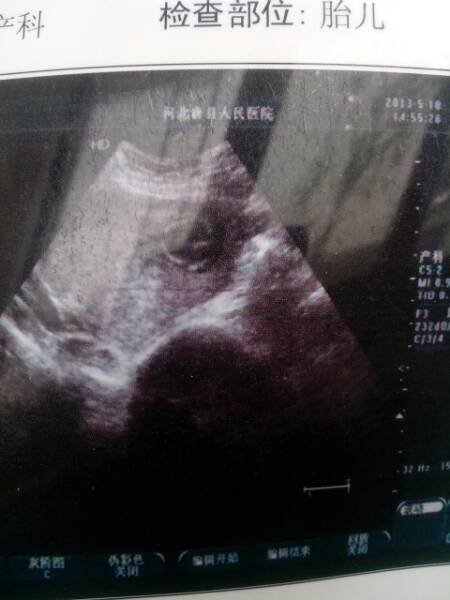

怀孕3个月bpd.1.7cm胎心动可见,后壁胎盘,羊水约4.0cm.懂的给看看谢谢 点击展开 匿名用户 2013-05-23 10:50 为您推荐: 其他回答 一切正常,安心养胎,注意加强营养即可 海鲜类的和动物肝脏类的,一周最多吃两次,吃多了容易胆固醇高,我之前吃的海鲜较多,检查的时候提示胆固醇高,医生告诉我少吃。 海带、紫菜可以天天吃,每天一斤牛奶(补钙和羊水的最佳食物) 能鹏赋_B5KL 2013-05-23 13:57 相关问题 怀孕4个月双顶径为4 0cm 股骨长2 7cm 胎心率150分钟一次 羊水暗区最深4 5cm胎盘附于子宫后壁厚1 6cm正常么 现在怀孕14周了,胎盘低、羊水32应注意什么?可以恢复吗? 怀孕5个月羊水有点偏多,胎盘有点下,什么原因?